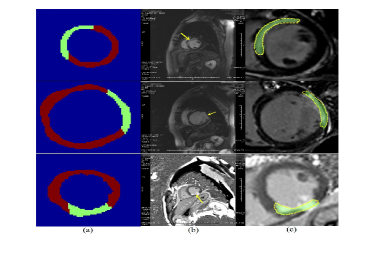

MI area detection. Our approach can also accurately detect the MI area, as shown in Fig. 2. The overall pixel classification accuracy is 94.35%, with a sensitivity of 91.23% and a specificity of 98.42%. We used the softmax classifier by fine-tuning the motion statistical layers to assess each pixel (as normal/abnormal). We also compared our results to 16 regional myocardial segments (depicted as normal/abnormal) by following the American Heart Association standards. The accuracy performance for the apical slices was an average of 99.2%; for the mid-cavity slices, it was an average of 98.1%; and for the basal slices, an average of 97.9%. The ROCs and PRs of the motion statistical layers are shown in Fig. 3 (a-b).